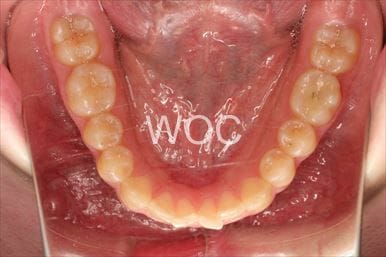

治療後3

- 年齢:20歳女性

- 主訴:出っ歯が気になる

- 基本矯正料金:120万円

- 治療期間:1年7ヶ月

- 抜歯部位:上顎両側第一小臼歯